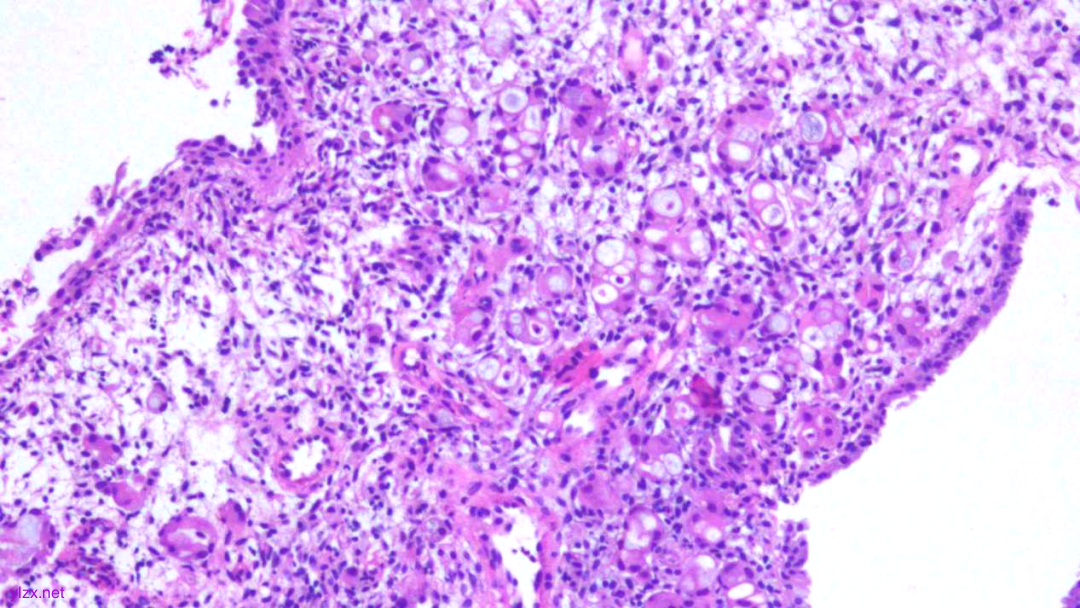

1.宫颈2点、10点:鳞状上皮下间质内见瘤组织弥漫增生,胞浆宽阔,红染,核小,较一致,部分细胞核偏位,部分细胞可见核仁;

2.宫颈5点:鳞状上皮下间质内见少量异型细胞巢,核增大,深染,浆红染,少量细胞浆内见黏液,印戒样;宫颈管搔刮组织:见血凝块、宫颈内膜组织,间质见异型细胞条索,形态同宫颈5点。

少量细胞浆内见黏液,印戒样

瘤细胞核偏位,浆红染

高倍瘤细胞见红色核仁